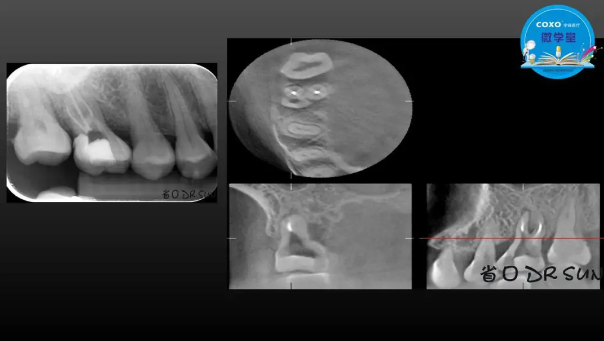

主講:孫書昱

主任醫(yī)師,牙體牙髓副主任, 廣東省口腔醫(yī)院牙體牙髓科 主任醫(yī)師。2003年碩士研究生畢業(yè),研究方向為牙體牙髓病學,擅長于牙體牙髓病的診斷、齲齒、牙髓炎、根尖周病的治療以及前牙美容修復。